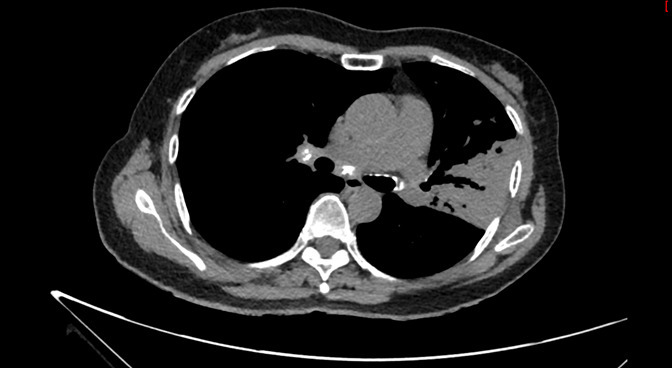

Un scanner thoracique est finalement réalisé devant cette toux chronique et l’altération de l’état général, dont voici quelques coupes :

Figure 2 (Jacques Durin, La Revue du Praticien)

Aspect de pneumopathie avec une condensation lobaire supérieure gauche et la présence d’un bronchogramme aérien dessinant l’arbre bronchique (flèche jaune).

Absence de liquide au contact de la condensation, pas de pleurésie déclive.

Le compte-rendu de radiologie décrit un aspect de pneumopathie lobaire supérieure gauche associée à des micronodules péri-bronchiolaires et des adénopathies médiastino-hilaires calcifiées.